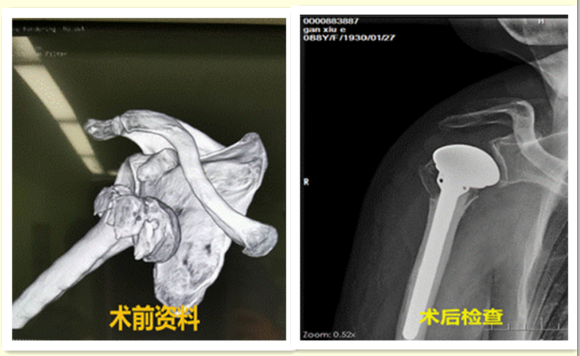

手术当日,张波主任凭借术前X线及CT等检查结果,先基本确定了假体粗略大小,术中则凭借丰富的临床经验进行了多点考量,如肱二头肌、三角肌张力,还有仅剩的一些残留骨性标志可以参考,最终快速的找到了合理的假体高度和准确的后倾角,为术后患者肩关节功能恢复最大化打下了坚实基础。历时1个多小时,手术顺利完成。